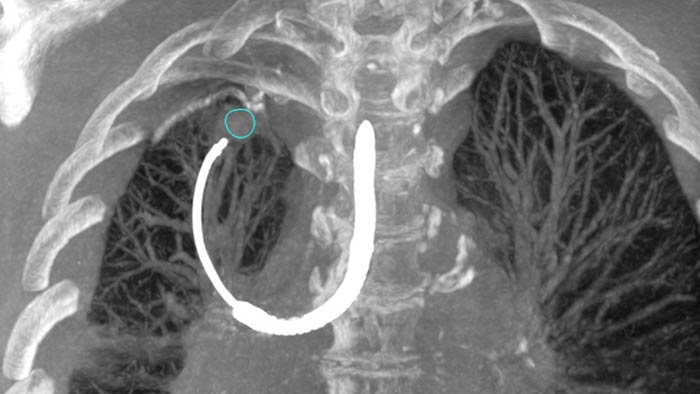

Excellent cone beam CT for lung cancer treatments.

Planning and guidance for percutaneous biopsy, marking and ablative therapy.